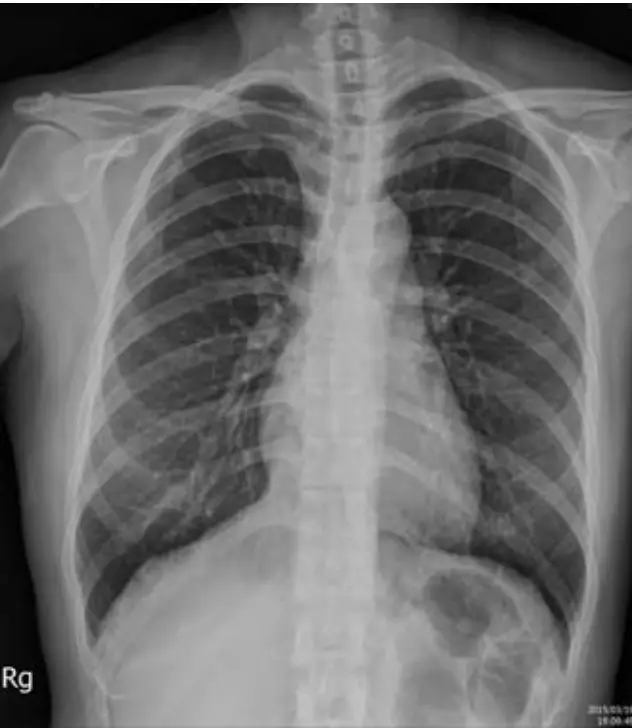

病人是位47歲家庭主婦,自7歲起就診斷有心臟病,18歲懷孕生有一子,過程尚稱順利,近十年來偶有心悸及胸悶,近二年曾有五次昏厥,因此住院。理學檢查及生化檢驗都正常。胸X光及心電圖(如圖)。本病人最有可能的診斷是:

本題考察心律不整的鑑別診斷,尤其是寬QRS波心搏過速(wide QRS complex tachycardia)的判讀。病人為47歲女性,自幼(7歲)即有心臟病史,近十年有心悸及胸悶,近二年有五次昏厥(syncope)。理學檢查與生化檢驗正常,搭配胸部X光與心電圖(含正常竇性心律與心搏過速發作時)進行診斷。正確答案為 (D) 來自右心室流出道的單形性心室頻脈(Monomorphic ventricular tachycardia from outflow tract,RVOT VT)。

影像分析:

圖一(胸部X光,PA view): 胸部後前位X光顯示心臟輪廓正常大小,肺野清晰,無肺水腫、肺充血或肺炎浸潤。無明顯心臟結構異常跡象。此發現與「理學檢查及生化檢驗都正常」相符,提示此心臟病可能並非結構性心臟疾病(structural heart disease),而是功能性心律不整。